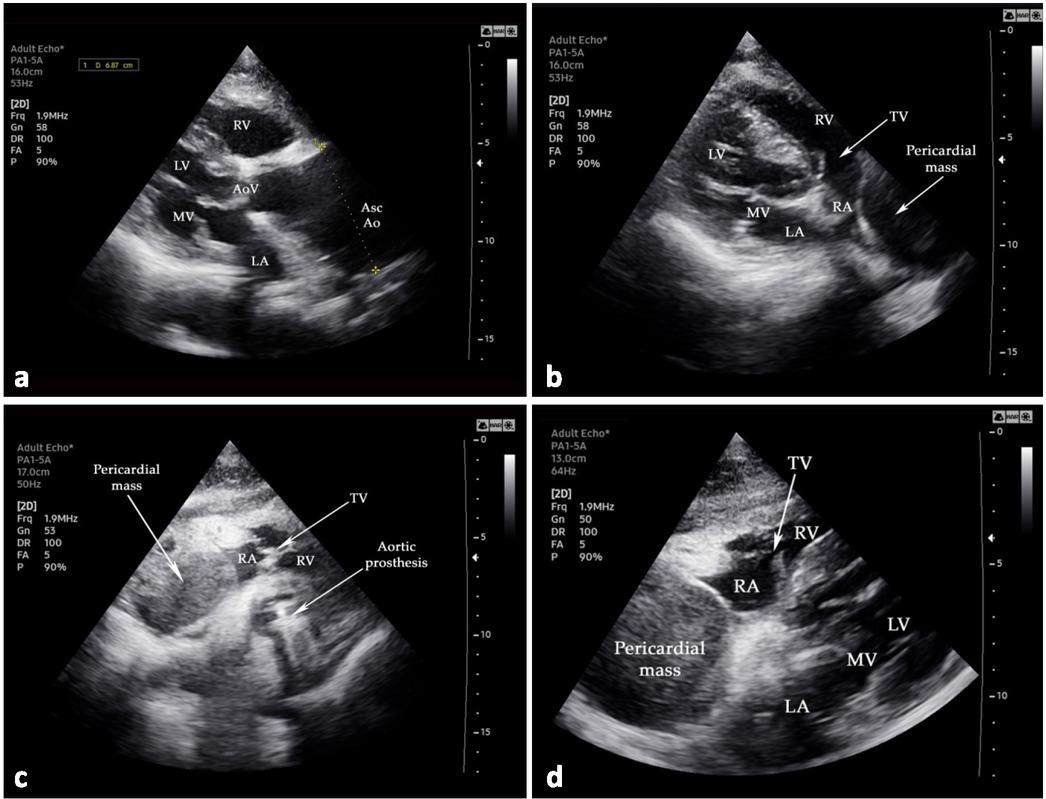

Fig. 1